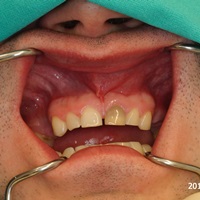

Wskazania do wykonania resekcji zębów 21, 22. Prawie niewidoczna blizna pooperacyjna.